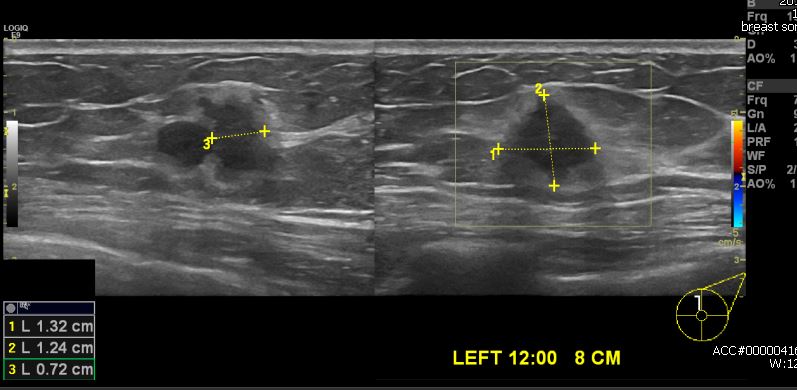

건강 검진상 이상소견으로 내원하신 50대 여성분으로 좌측 12시 방향에서 8cm 떨어진 거리의 혹 조직검사 시행 하였고 좌측 침윤성 유방암 진단 되었습니다.